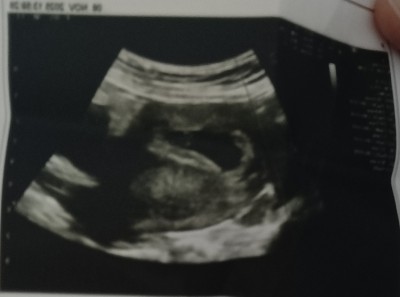

image

Hanımlar çok şükür oğlum da var kızım da var . Allah herkese nasip etsin.ama yine de merak ediyorum.bir çok teori varmış sizce kese şekline göre bebeğin cinsiyeti nedir.

Gebelik haftası 8